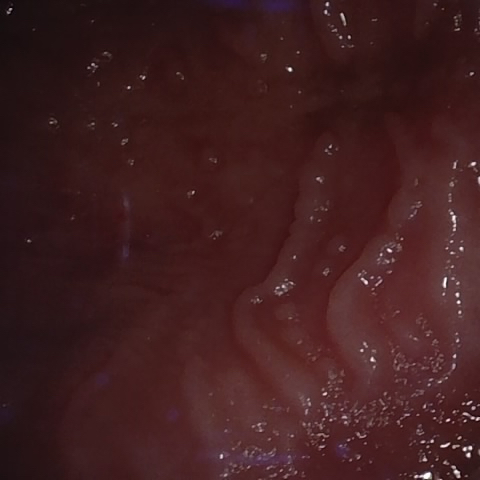

NHD39174

Overview

Annotated as "Good"